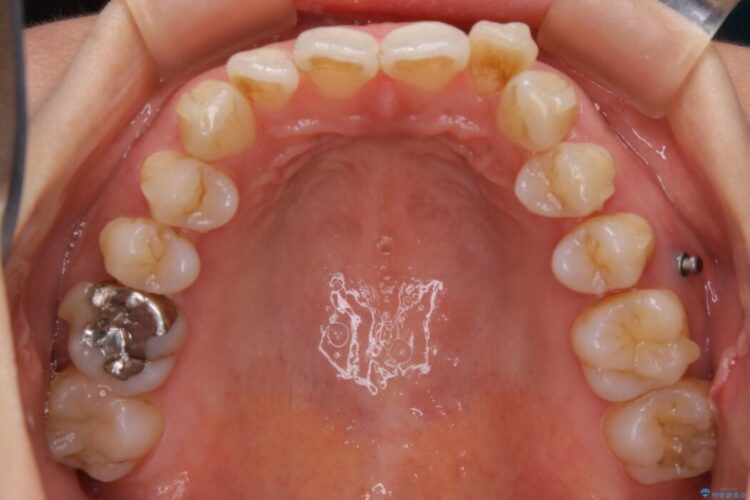

ですが、上顎左側の歯が前方へ寄っている状態であるため噛み合わせにズレが生じていました。

よって噛み合わせのズレをマイクロインプラントを使用して歯を移動させ、インビザラインにて歯列の整えを行うこととしました。